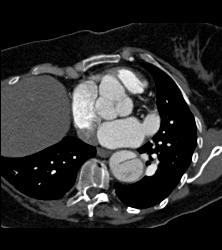

Dilated Sinus of Valsalva and Dissection